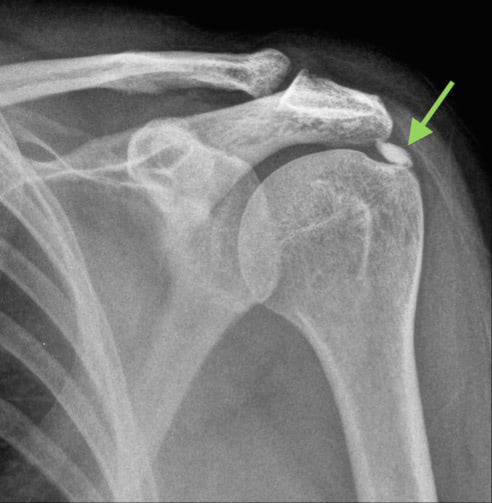

Calcific tendinitis, also known as calcific tendinopathy, is a condition where calcium deposits form in the rotator cuff of the shoulder. It occurs most often in the supraspinatus tendon, but can occur in any of the shoulder tendons, and even other tendons such as the elbow and wrist.

- This stage involves the formation of calcium deposits